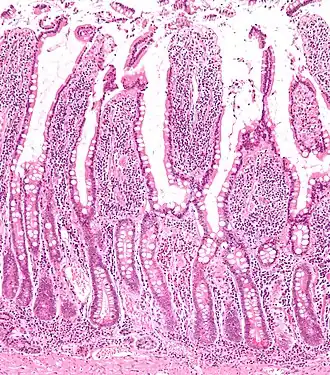

The three sections of the small intestine look similar to each other at a microscopic level, but there are some important differences. The parts of the intestine are as follows:

| Mucosa: intestinal epithelium | Simple columnar. Contains goblet cells, Paneth cells | Similar to duodenum, but the intestinal villus is long | Similar to duodenum, but the intestinal villus is short |

Digested food is now able to pass into the blood vessels in the wall of the intestine through either diffusion or active transport. The small intestine is the site where most of the nutrients from ingested food are absorbed. The inner wall, or mucosa, of the small intestine, is lined with intestinal epithelium, a simple columnar epithelium. Structurally, the mucosa is covered in wrinkles or flaps called circular folds, which are considered permanent features in the mucosa. They are distinct from rugae which are considered non-permanent or temporary allowing for distention and contraction. From the circular folds project microscopic finger-like pieces of tissue called villi (Latin for "shaggy hair"). The individual epithelial cells also have finger-like projections known as microvilli. The functions of the circular folds, the villi, and the microvilli are to increase the amount of surface area available for the absorption of nutrients, and to limit the loss of said nutrients to intestinal fauna.

Each villus has a network of capillaries and fine lymphatic vessels called lacteals close to its surface. The epithelial cells of the villi transport nutrients from the lumen of the intestine into these capillaries (amino acids and carbohydrates) and lacteals (lipids). The absorbed substances are transported via the blood vessels to different organs of the body where they are used to build complex substances such as the proteins required by our body. The material that remains undigested and unabsorbed passes into the large intestine.